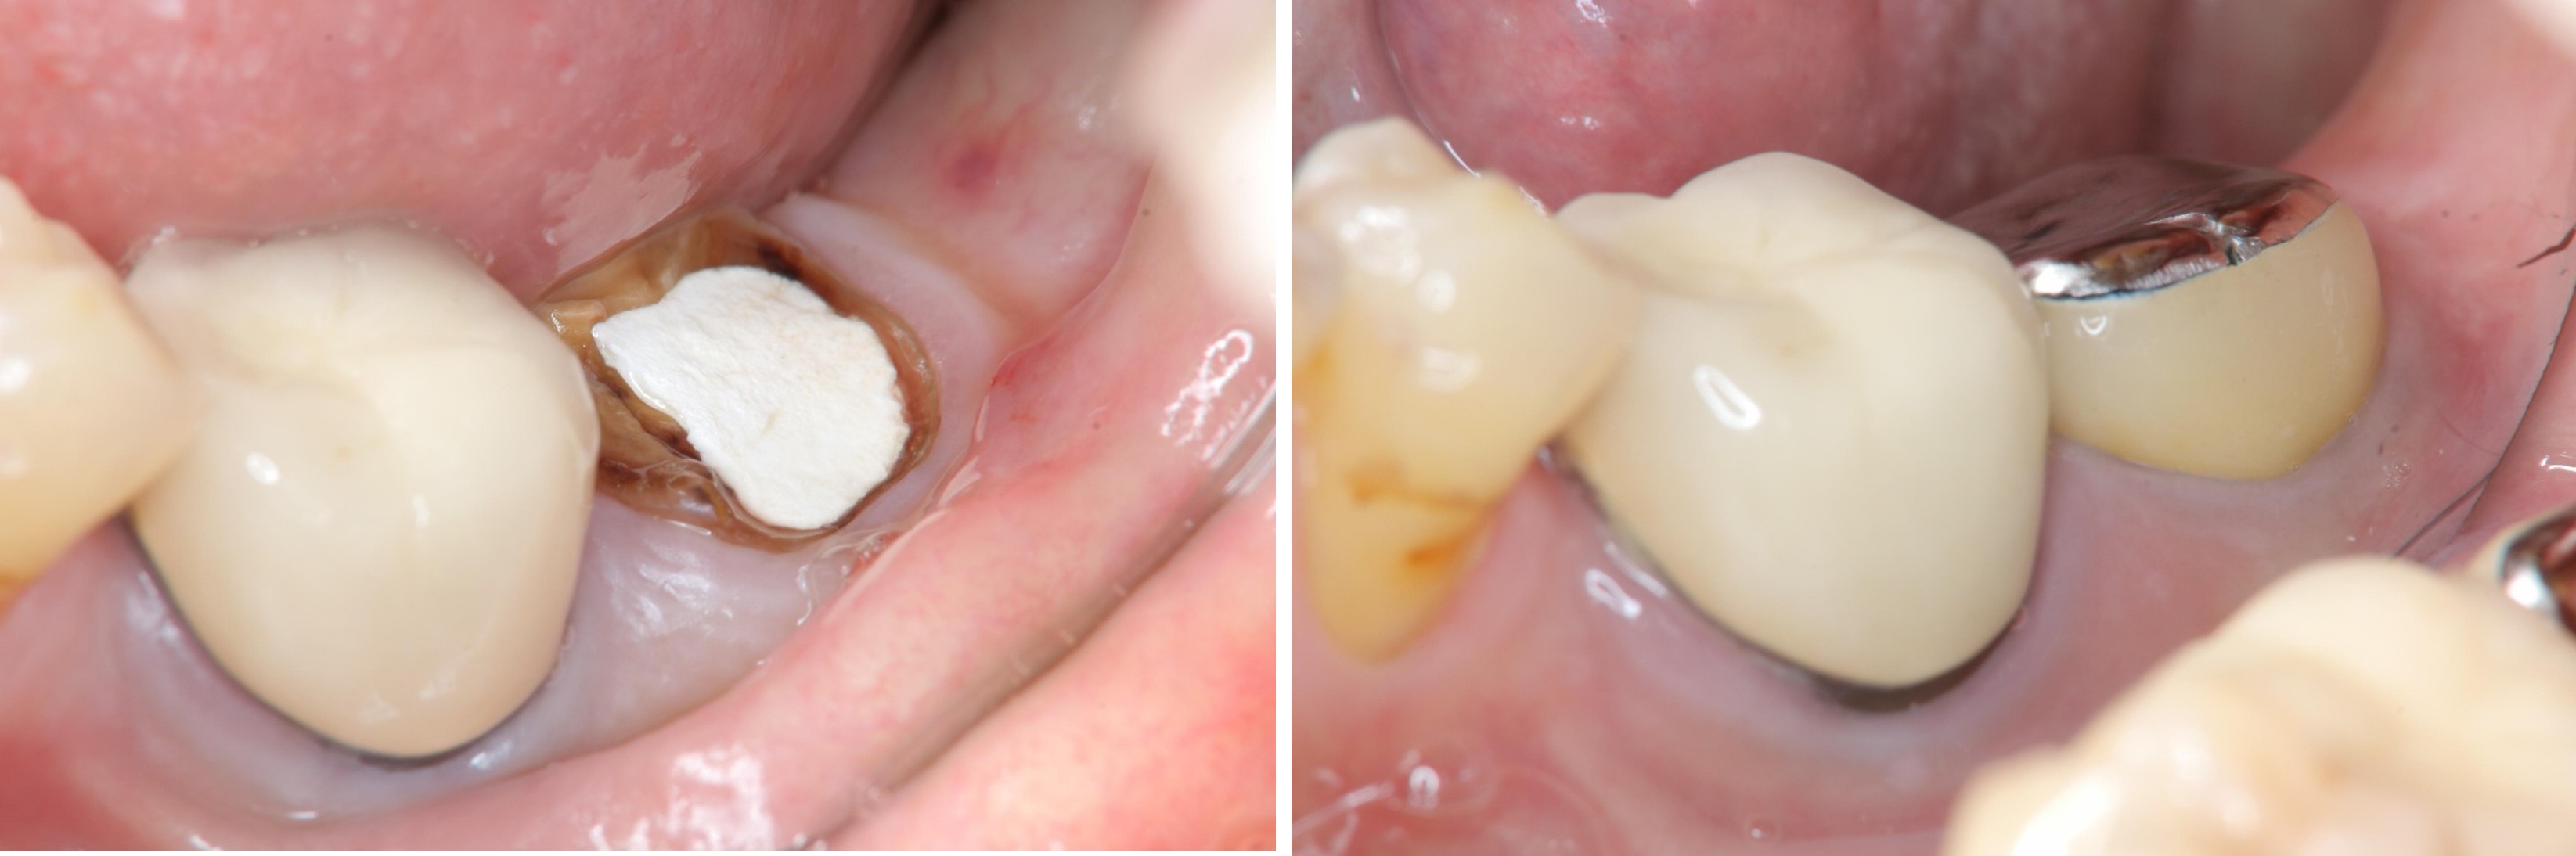

牙齒印模前追蹤

治療後口內照

術前、術後比較